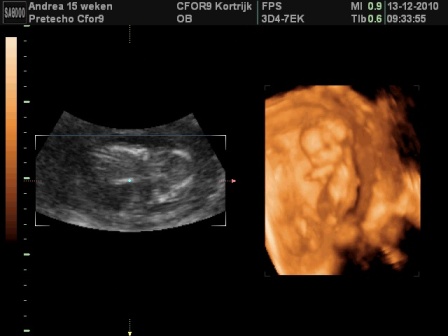

Tegnapi UH:

CRL = 48 mm.

A kombinált teszt 15-én lesz.